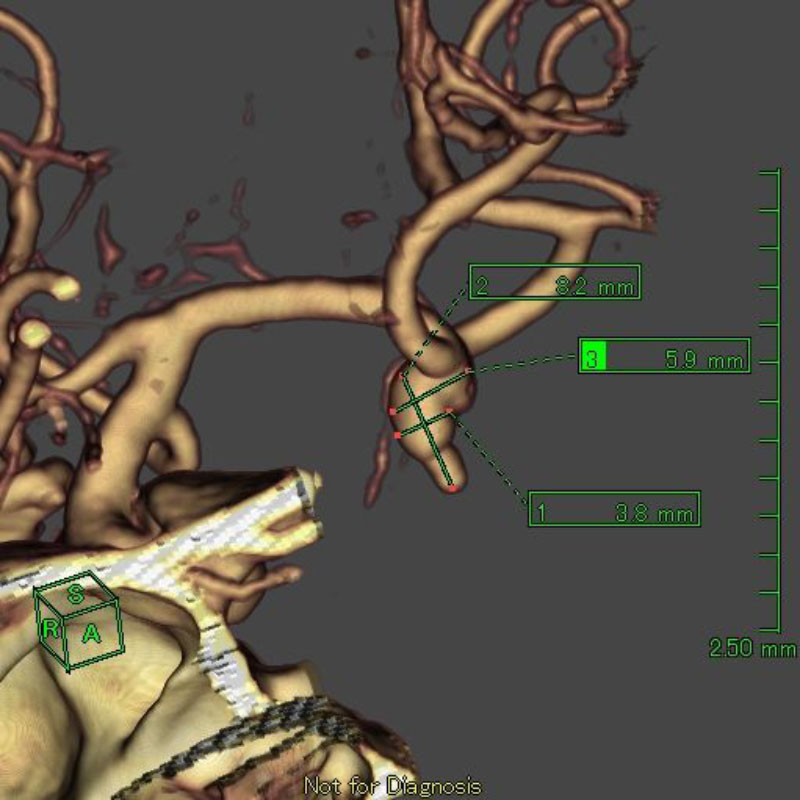

2

'26年1月

50代

右中大脳動脈瘤

クリッピング術

手術前

クリップ前

クリップ後

術後血管撮影